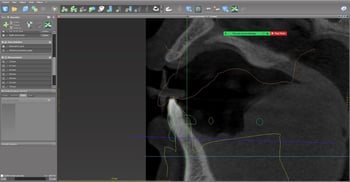

After capturing the intraoral scan (Fig. 3), the laboratory superimposed the CBCT and IOS data. Using my clinical input, the team digitally simulated anterior tooth placement (Fig. 4), supporting a predictable digital denture workflow.

With the proposed tooth position defined, we predicted the ideal lower occlusal plane, which revealed the need for significant bone reduction.

Our primary objective was to achieve proper vertical dimension and sufficient restorative space to support a future implant overdenture, with a minimum clearance of 12–15 mm.

Computer-generated surgical guides were then used to facilitate precise bone reduction in both arches, reinforcing the value of prosthetic-driven planning.